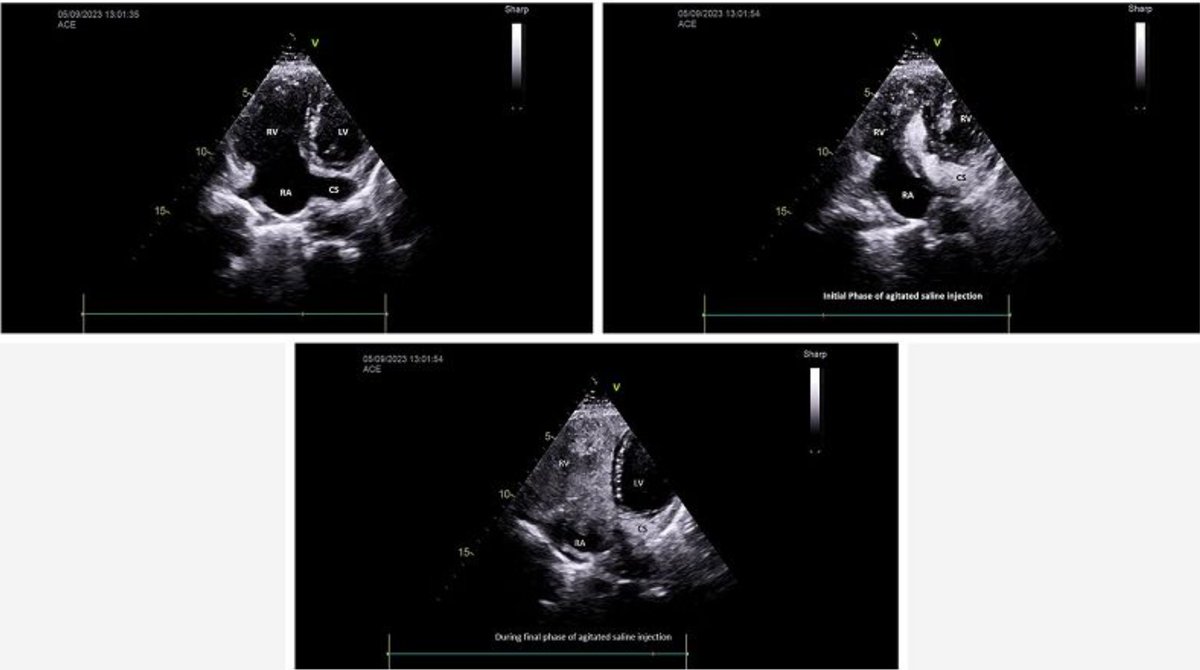

#ImageoftheWeek This #Quiz was submitted by Bishal KC, Samir Gautam and Sachin Dhungel from the Gautam Buddha Community Heart Hospital, Butwal,🇳🇵 What does this agitated saline contrast echocardiography via left cubital vein show? ☑️shorturl.at/NRTmn @EACVIPresident

echo_stepbystep's tweet image. #ImageoftheWeek This #Quiz  was submitted by Bishal KC, Samir Gautam and Sachin Dhungel from the Gautam Buddha Community Heart Hospital, Butwal,🇳🇵

What does this agitated saline contrast echocardiography via left cubital vein show?